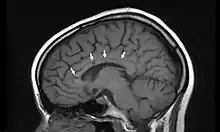

| Sagittal T1 image in a 19-year-old woman with Susac's syndrome showing the pathognomonic central callosal "holes" (microinfarcts) of SS. These residual "holes" (and sometimes, "spokes") develop as the acute callosal changes resolve. | |

Radiographic appearance

In a recent analysis (Susac et al., 2003), MRI images from 27 patients fulfilling the diagnostic criteria of Susac's syndrome were reviewed. Multifocal supratentorial lesions were present in all patients. Most lesions were small (3 to 7 mm), though some were larger than 7 mm. All 27 patients had corpus callosum lesions. These all had a punched-out appearance on follow-up MRI. Though most commonly involving white matter, many patients also had lesions in deep grey matter structures, as well as leptomeningeal enhancement. Multiple sclerosis (MS) and acute disseminated encephalomyelitis (ADEM) can mimic the MRI changes seen in patients with Susac's syndrome. However, the callosal lesions in Susac's syndrome are centrally located. In comparison, patients with MS and ADEM typically have lesions involving the undersurface of the corpus callosum. Deep gray matter involvement commonly occurs in ADEM but is very rare in MS. Leptomeningeal involvement is not typical of either MS or ADEM: if 10 lesions are found in the brain of an MS patient, a lesion may be found in the corpus callosum. If a Susac patient has 10 lesions, more than half will be in the corpus callosum.